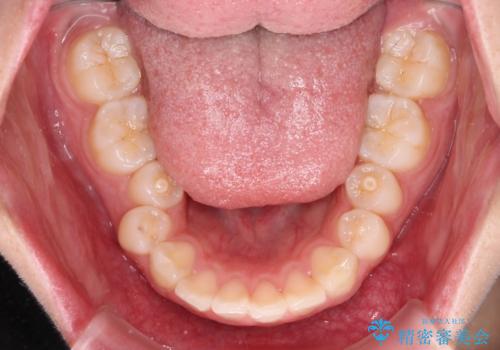

- 飛び出した上顎前歯と、閉じにくい唇、口元の突出した印象の横顔を気にして来院された患者様です。

骨格的な上顎前突であり、上下前歯の前後的な距離が大きいため、上顎は左右第一小臼歯を、下顎は左右第二小臼歯をそれぞれ2本抜歯することで前歯が接触するようにし、さらには奥歯の咬み合わせも、より理想的な状態へ近づけていくこととしました。

事前の予想通り、長期間を要する治療となりましたが、横顔の印象が劇的に変化し、患者様には大変満足していただきました。